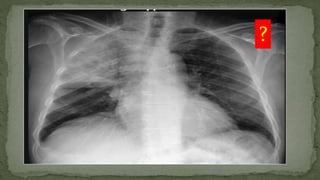

Right Pneumothorax

?

Consolidation Right